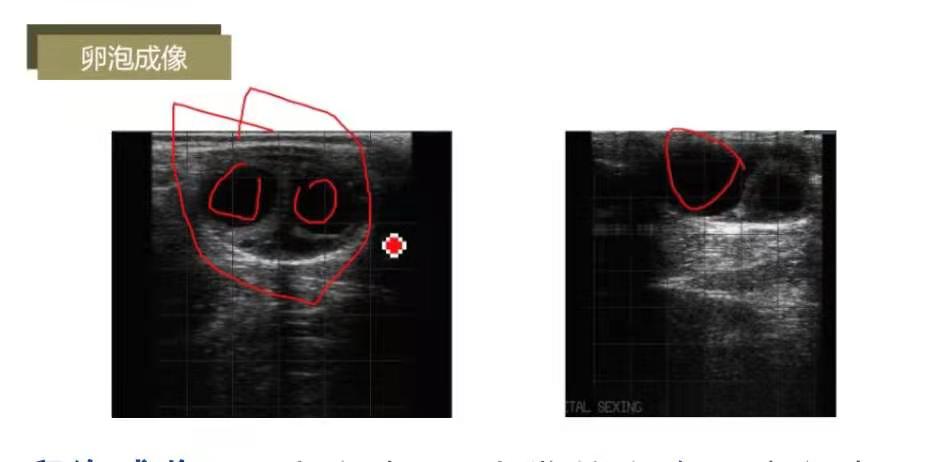

卵巢成像:卵巢灰色,黑色为卵泡内液体;因无卵泡,显示灰色;含2个卵泡。

卵泡成像:2个卵泡;1个发情卵泡,直径在2cm左右。